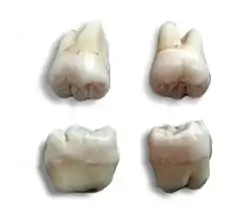

Morphology of wisdom teeth can be variable.

Maxillary (upper) third molars commonly have a triangular crown with a deep central fossa from which multiple irregular fissures originate. Their roots are commonly fused together and can be irregular in shape.

Mandibular (lower) third molars are the smallest molar teeth in the permanent dentition. The crown usually takes on a rounded rectangular shape that features four or five cusps with an irregular fissure pattern. Roots are greatly reduced in size and can be fused together.[7]